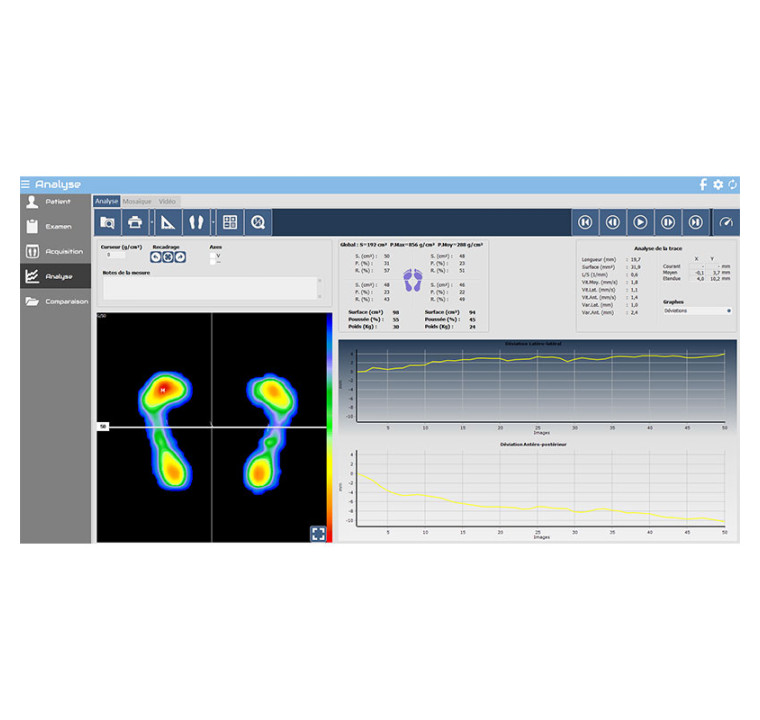

This CD is used to update the Presscam™ or Presscam™ Wi-Fi plantar pressure platform, and also offers a 2-year support contract.

UPDATE AND 2-YEAR SUPPORT CONTRACT for the Presscam™ and Presscam™ Wi-Fi plantar pressure platforms.